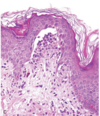

what is seen in the image and what condition is characterized by these lesions?

on microscopic examination of Lichen Planus, ____ show degeneration and necrosis which leads to an angular contour/\_\_\_\_ of the rete ridges

on microscopic examination of Lichen Planus, **basal keratinocytes** show degeneration and necrosis which leads to an angular contour/**saw-toothing** of the rete ridges

on microscopic examination of Lichen Planus, there are dense, continuous ____ infiltrate at the ___ junction

on microscopic examination of Lichen Planus, there are dense, continuous **lymphocytic** infiltrate at the **dermo-epidermal** junction

describe the image and the condition it is seen in

**lichen planus**